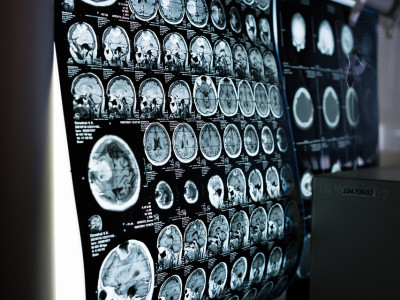

My response: I began my career working for a medical assistance company, helping people in exactly these kinds of circumstances. Not only do I have an awareness of the medical and nursing management of patients recovering in critical care, but I am well-versed in the language of the medical imaging techniques used for assessment. Here, brain CT scans were used to monitor the patient's progress and the extremely high-level terminology was crucial to get right.